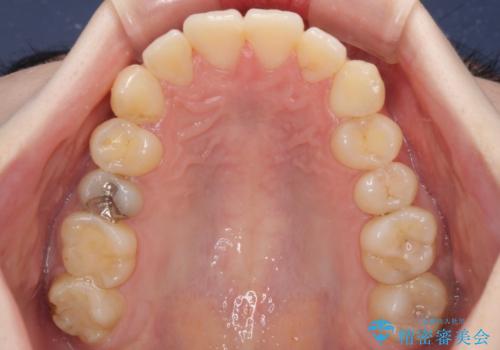

デコボコ歯列をきれいに インビザラインによる矯正治療

- 上下歯列全体のデコボコを気にして来院された患者様です。

主に下顎歯列全体の後方移動とIPR(歯と歯の間を削る)によってデコボコが解消するように設計し、インビザラインにより治療を行うこととしました。

奥歯の知覚過敏が顕著となり、その影響で奥歯の咬み合わせ改善のための顎間ゴムの装着ができず、咬合を仕上げるまでに長い期間を要することとなりました。